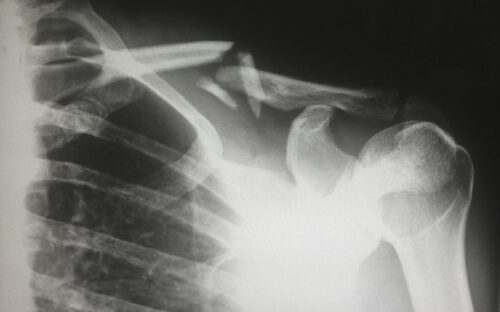

It’s also important to understand that there are many different types of fractures that can impact the severity of the injury. For example, you’ll find that a hairline fracture, which occurs when a crack forms in the bone but does not break all the way through, will heal much faster than an open fracture, which occurs when a bone breaks and a portion pierces through the skin so the bone is visible. However, there are also spiral fractures, unstable fractures, and stable fractures.